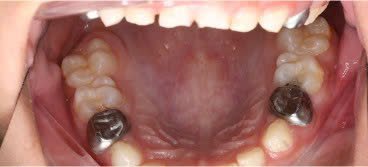

SSC (Stainless Steel Crown) là mão răng bằng thép không gỉ, được thiết kế sẵn với nhiều kích cỡ khác nhau, thường dùng để phục hồi răng sữa đã bị sâu lớn hoặc tổn thương nặng. Đây là một dạng phục hình toàn phần bao phủ toàn bộ thân răng, giúp bảo tồn và duy trì chức năng của răng sữa cho đến khi thay răng vĩnh viễn.

Duy trì được răng sữa đến đúng thời điểm thay răng, ngăn ngừa mất khoảng và sai lệch cung răng.

Giúp răng giữ chức năng nhai, phát âm và thẩm mỹ trong giai đoạn phát triển.

- Bảo vệ răng sau điều trị tủy

Mão SSC giúp bao phủ toàn bộ thân răng, giảm nguy cơ nứt vỡ và tái nhiễm khuẩn.